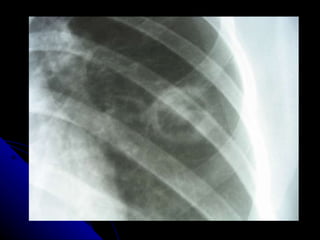

TEP